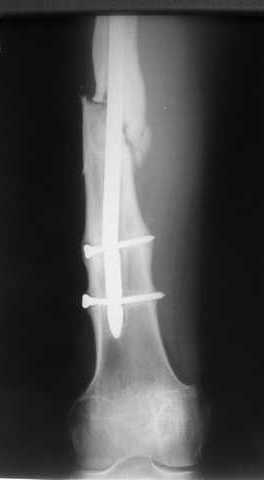

В приложении как раз видна эволюция использововшихся у нас большеберцовых гвоздей. Первый - дизайн как у UTN, второй - разнесены 45 градусные отверстия (зачем их вообще изначально так нелепо на одном уровне сделалм???), третий - убрано сиавшее лишним статическое отверстие, Herzog's bend перемещен более проксимально.